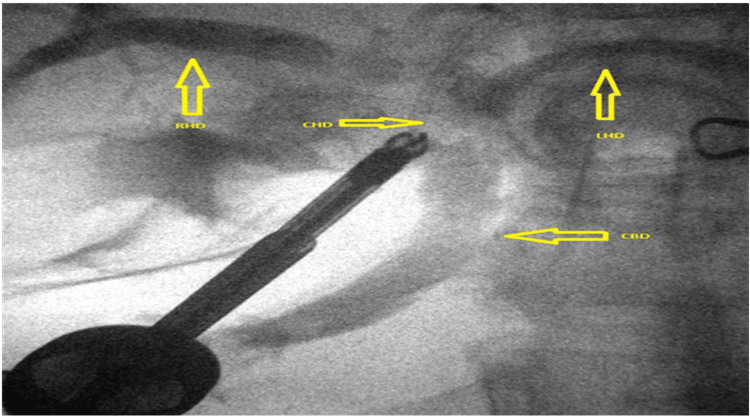

Subsequent exploration revealed that Hartmann’s pouch of the gallbladder was closely abutting the CHD, suggestive of Mirizzi syndrome (Figure 3), further complicating the surgery. During the procedure, an additional duct-like lumen draining bile was discovered in continuity with the gallbladder, raising suspicion for an anatomical variant (Figure 4). Due to this unexpected finding, an intraoperative cholangiogram (IOC) was performed, which confirmed the patency and integrity of the common bile duct (CBD), CHD, and both right and left hepatic ducts, as demonstrated in Figure 5.

To aid in anatomical clarification and to prevent potential bile duct injury, we performed an IOC. The IOC confirmed the patency of the CBD, CHD, and intrahepatic ducts, and delineated the presence of two cystic ducts draining a single gallbladder. The IOC is widely regarded as a valuable tool for distinguishing ductal anomalies from bile duct injuries during surgery. It not only maps the biliary tree but also detects retained stones and clarifies ambiguous anatomy [ref. 19].